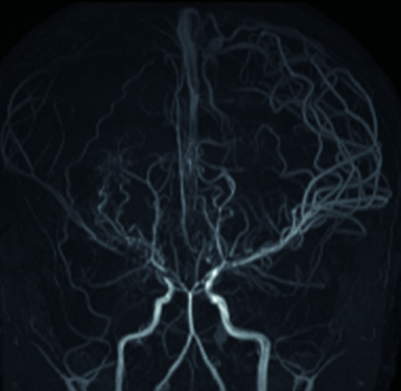

▪️ MRI (자기공명영상) : 뇌의 구조와 혈류 상태를 평가하는 데 사용됩니다.

▪️ MRA (자기공명혈관조영술) : 뇌혈관의 상태를 자세히 확인할 수 있습니다.